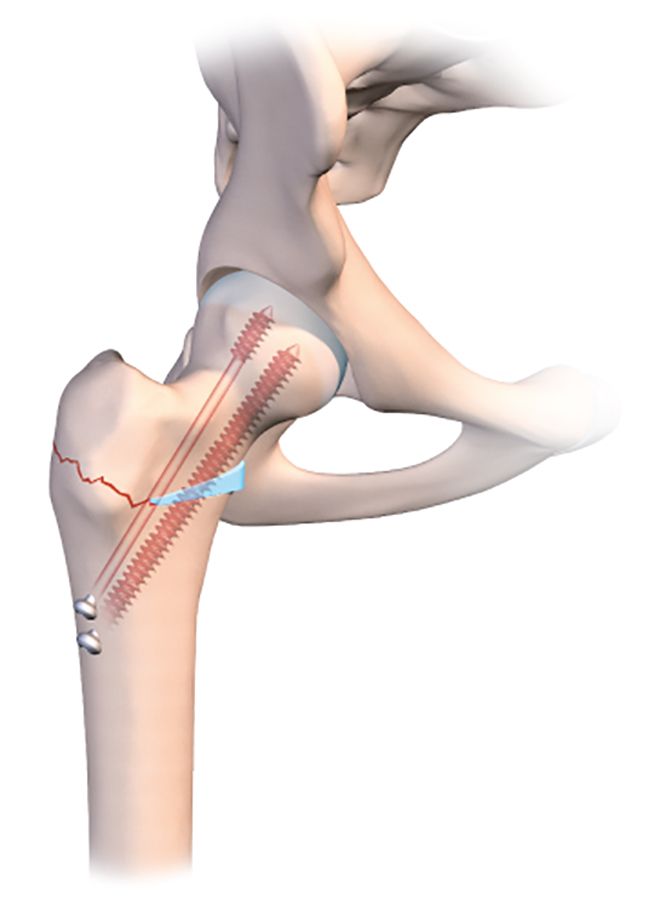

For a valgus-producing osteotomy, the technique is even simpler. One single osteotomy line is required in the medial half of the femur (Fig. 3a).

Simply applying traction along the line of the femur will naturally cause the osteotomy line to open. The line should be incomplete, and the lateral part should again be created as for a guided bone fracture. The medial section of the line is then opened by putting the orthopaedic table in traction.

However, the fixation process is trickier, because the cannulated screw must not create any new compression which would close the line (Figs. 3b, c, d). I recommend using a large diameter fully-threaded cortical screw as close as possible to the medical cortex into the femoral neck where the bone stock quality is highest. A second more lateral screw will maintain a good degree of compression on the lateral part of the line. In addition, here the screw will embed into the cancellous bone of the greater trochanter.

It is quite possible and even desirable to improve the outcome and avoid any loss of correction upon weight-bearing, to insert a hydroxyapatite wedge into the open line (Fig. 3e).

A wedge could be harvested from the iliac crest in order to fill the gap, but this would be insufficient on its own to produce the desired degree of valgus. When the patient tries to bear weight on the region, the line will be unable to close and crush the wedge. The medial-most fully-threaded screw will be more effective if seated in the lateral cortex of the lateral diaphysis and firmly embedded in the head.